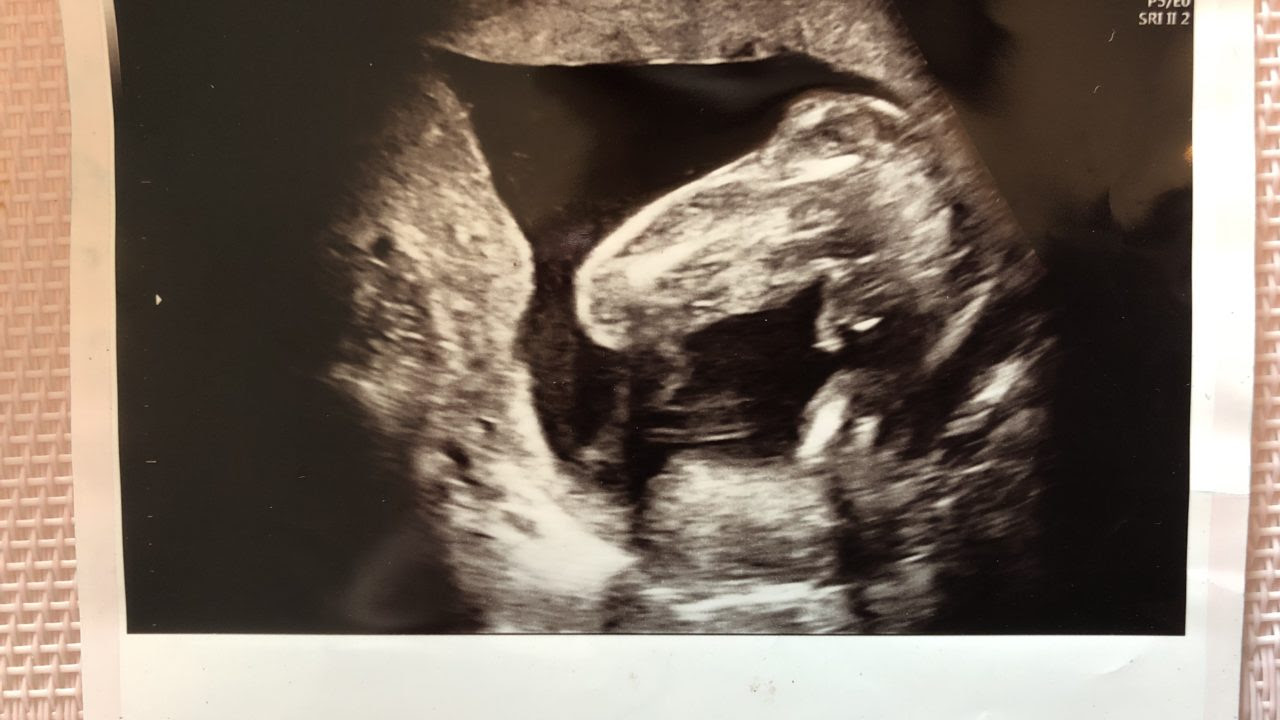

妊娠24週目です!エコー写真の性別どちらだと思いますか?先生は女の子だ 妊娠24週目です! エコー写真の性別どちらだと思いますか? 先生は女の子だと思うがもっこりしてるって言うんです笑 どういう意味だろうと思って謎です! よろしくお願いします!週時のエコー画像で、性別判断お願いします。 週の検診時、性別を知りたい 2 今日週0日です。今日検診にいき、〜23週の間に使える妊婦健康検査診断表という券を使い受診予定 3 初回妊婦検診の血液検査についてお願いします。 現在妊娠12週6日の妊婦16週 女の子 エコー写真 16週 エコー 突起物 女の子 ~ すべての 赤ちゃんの性別について yoshimichan0905さん 今12週の妊婦です。 今日の検診でお腹からの エコーで、男の子シンボル らしき物が見えました。

週 性別 女の子 エコー 妊娠週は、妊娠期を40週とした場合ちょうど半分まで来たことになります。ますます大きくなるお腹、人間らしくなる赤ちゃん。ママもパパも「親になる」という実感がだんだん湧いてくる頃ではないでしょうか。妊娠24週ってどんな時期?! エコーで赤ちゃんの性別が確定できました♡女の子の場合でも断定できる!葉っぱマークや子宮が見えるって本当?? そしてツワリも終わって気をつけたいのが体重管理!! 妊娠中の体重増加の目安って?ツワリで減った場合は、どの時点の体重から考えるべき?